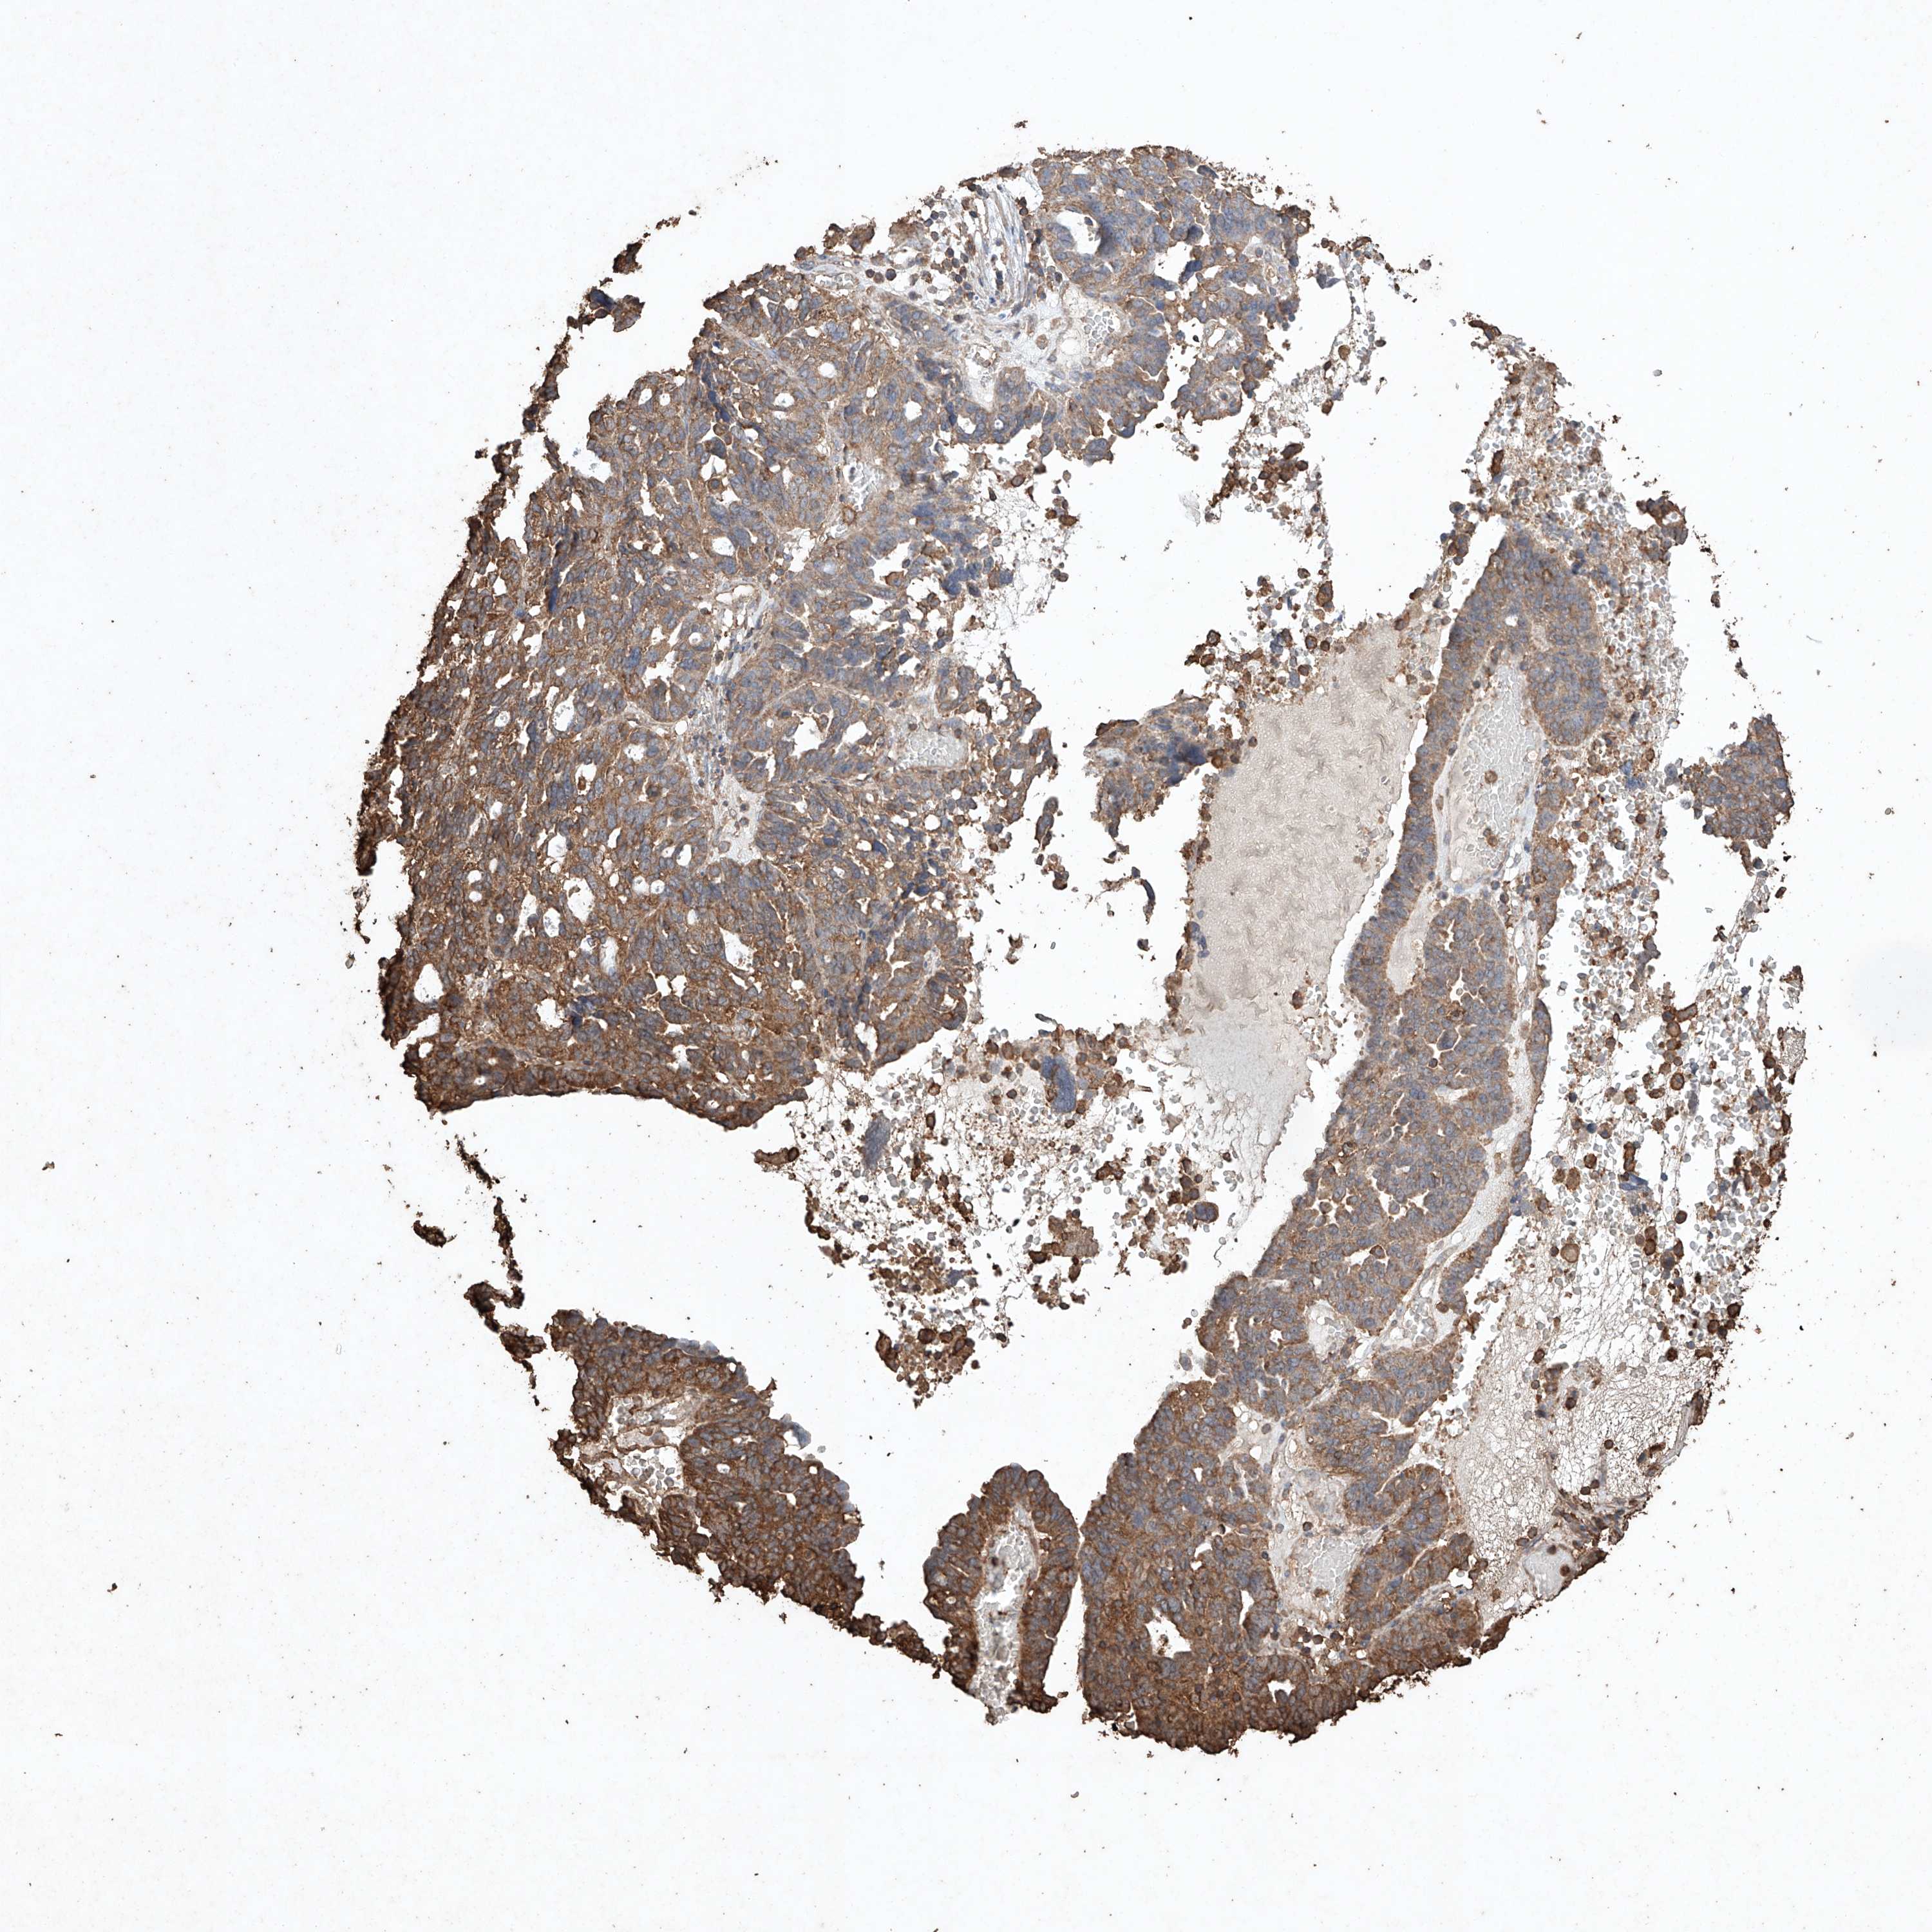

OVARIAN CANCER - Protein expressioni

A mouse-over function shows sample information and annotation data. Click on an image to view it in a full screen mode. Samples can be filtered based on level of antibody staining by selecting one or several of the following categories: high, medium, low and not detected. The assay and annotation is described here.

Note that samples used for immunohistochemistry by the Human Protein Atlas do not correspond to samples in the TCGA dataset.

Antibody stainingi

Antibody staining in the annotated cell types in the current human tissue is reported as not detected, low, medium, or high, based on conventional immunohistochemistry profiling in selected tissues. This score is based on the combination of the staining intensity and fraction of stained cells.

Each image is clickable and will lead to virtual microscopy that enables deeper exploration of all samples and also displays staining intensity scores, fraction scores and subcellular localization as well as patient and tissue information for each sample.

Antibody HPA040445

Antibody CAB034464

Staining

High

Medium

Low

Not detected

Intensity

Strong

Moderate

Weak

Negative

Quantity

>75%

75%-25%

<25%

None

Location

Nuclear

Cytoplasmic/membranous

Cytoplasmic/membranous,nuclear

Carcinoma, NOS